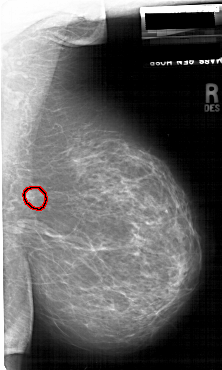

A_1745_1.RIGHT_CC

RIGHT_CC LINES 6601 PIXELS_PER_LINE 3601 BITS_PER_PIXEL 12 RESOLUTION 43.5 OVERLAY

FILE: A_1745_1.RIGHT_CC.OVERLAY

TOTAL_ABNORMALITIES 1

ABNORMALITY 1

LESION_TYPE MASS SHAPE IRREGULAR MARGINS ILL_DEFINED

ASSESSMENT 4

SUBTLETY 2

PATHOLOGY BENIGN

TOTAL_OUTLINES 1

BOUNDARY